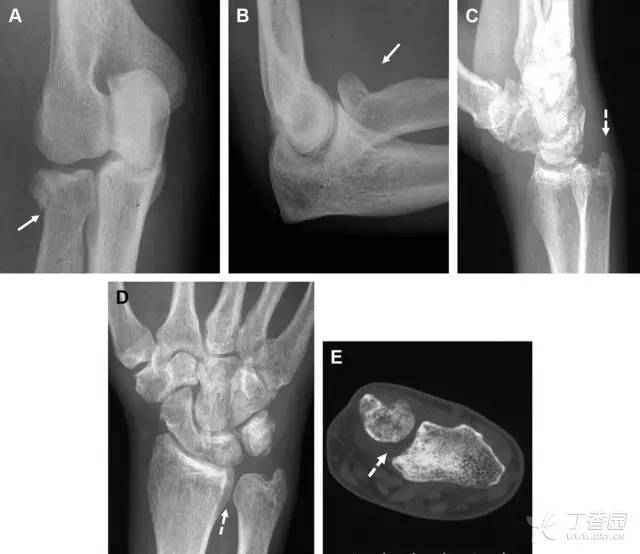

24 无移位的桡骨头/颈骨折

多发生于摔倒时,手掌撑地,受到轴向、外翻应力所致。常规的前后位片容易漏诊,常需加拍内斜位、外斜位、桡骨头-肱骨小头位片。后脂肪垫可见(位于鹰嘴窝内,一般不可见)和/或前脂肪垫抬高常提示骨性损伤。

图 2 桡骨头骨折。前后位(A)和侧位(B)片示后脂肪垫抬高(黑色箭头),前脂肪垫抬高(白色箭头),呈「帆船征」,其它表现正常;外斜位(C)和桡骨头–肱骨小头位(D)示桡骨头关节内骨折线(虚线黑箭头)累及桡骨颈(虚线白箭头)